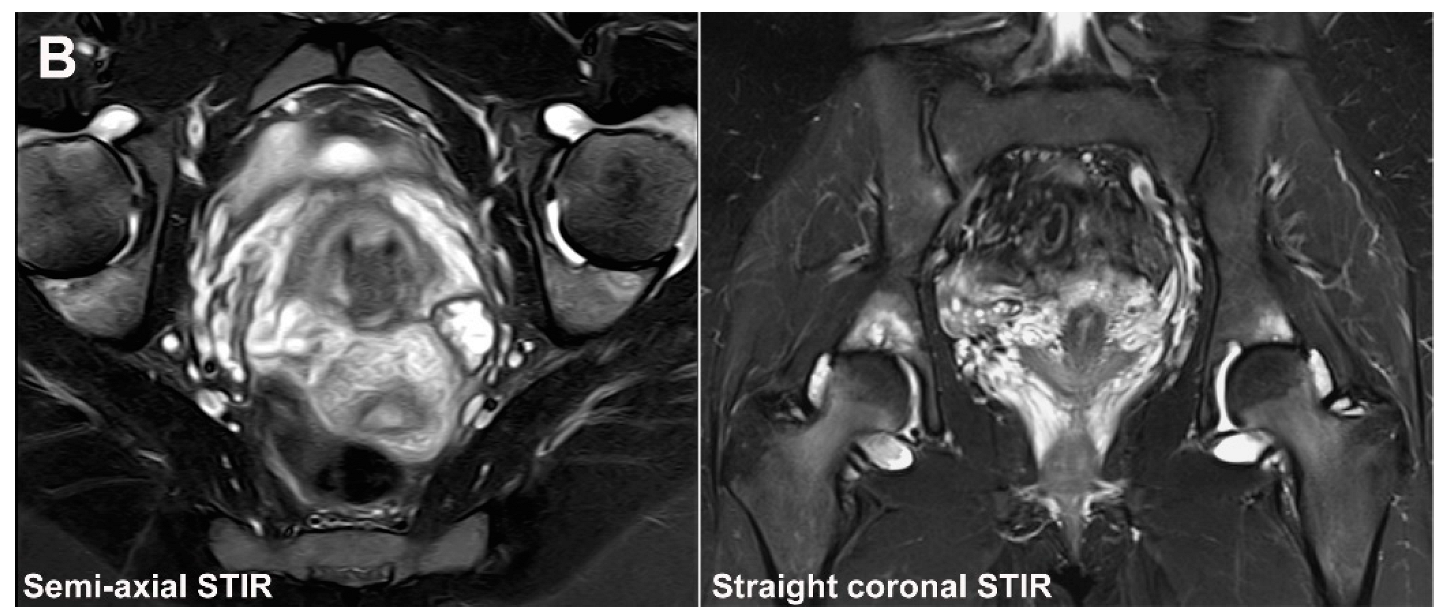

- Weber, U.; Jurik, A.G.; Zejden, A.; Larsen, E.; Jørgensen, S.H.; Rufibach, K.; Schioldan, C.; Schmidt-Olsen, S. MRI of the Sacroiliac Joints in Athletes: Recognition of Non-Specific Bone Marrow Oedema by Semi-Axial Added to Standard Semi-Coronal Scans. Rheumatology 2020, 59, 1381–1390. [Google Scholar] [CrossRef]